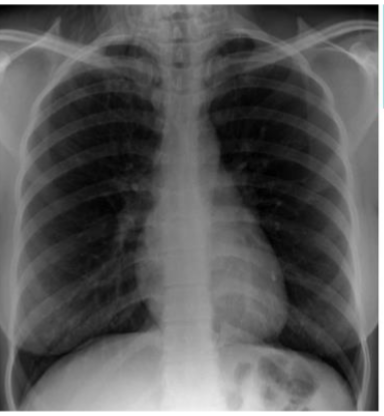

PA CXR

Label this CXR (10 things)

1) trachea 2) hilum- should have R and L 3) lungs 4) diaphragm 5) heart 6) aortic knuckle 7) ribs 8) scapulae 9) breasts 10) bowel gas